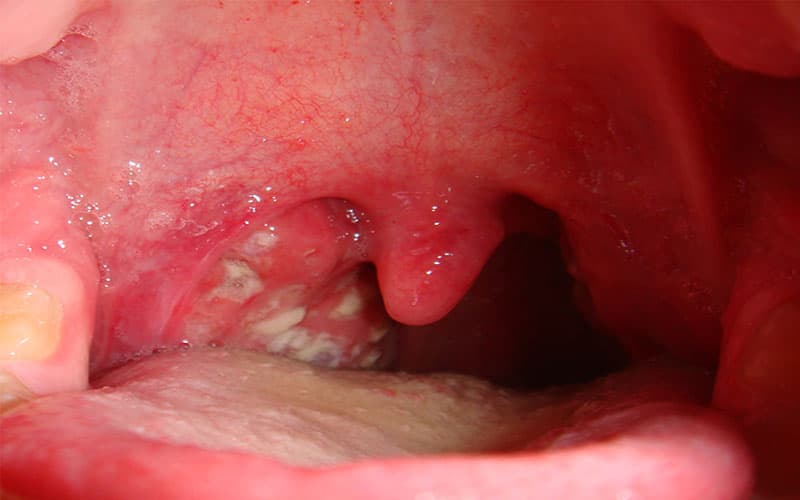

Bệnh bạch hầu (hay Diphtheria) là một bệnh nhiễm trùng cấp tính gây ra sự hình thành giả mạc dày và trắng ngà, lan rộng trên vòm họng, mũi, tuyến hạnh nhân và thanh quản. Bệnh cũng có thể xuất hiện trên da và các niêm mạc khác như kết mạc mắt và bộ phận sinh dục.

– Bệnh bạch hầu họng và amidan: Người mắc bệnh sẽ có triệu chứng đau họng, mệt mỏi, mất khẩu vị và sốt nhẹ. Sau 2-3 ngày, xuất hiện một lớp giả mạc màu trắng xanh, dai và dính chắc vào amidan hoặc có thể lan rộng và bao phủ cả vùng họng. Trong một số trường hợp, bệnh nhân có thể bị sưng nề vùng dưới hàm và sưng các hạch vùng cổ, làm cổ bạnh ra như cổ bò.